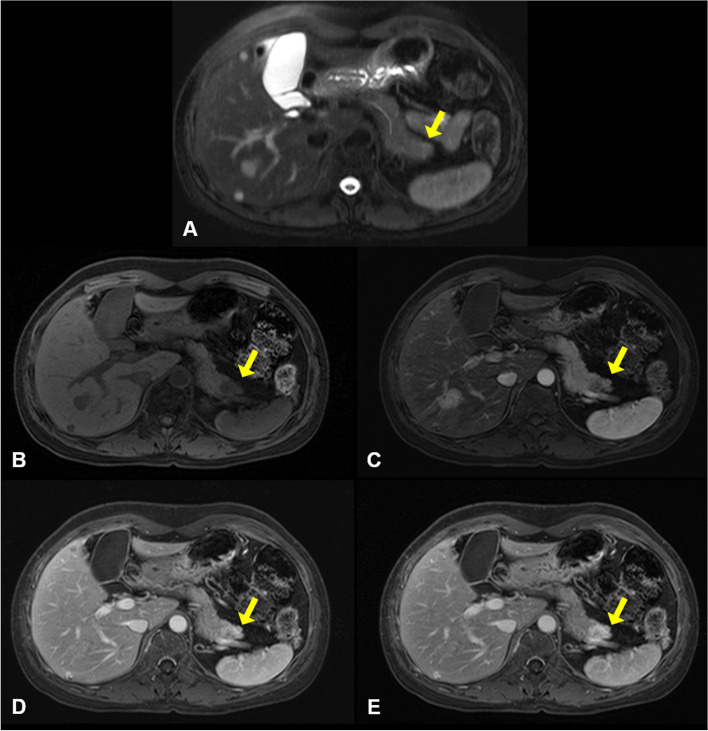

A 49-year-old woman was referred to our institution with a liver mass of 3 cm diameter that was incidentally identified on abdominal computed tomography during a medical check-up. She had been diagnosed with bilateral breast cancer at the age of 30, when she underwent bilateral modified mastectomy. Abdominal MRI revealed two masses in both the liver and pancreas. The mass in the right hepatic lobe (segment 6) demonstrated low signal intensity on T1‑weighted images (Fig. 1A) and intermediate signal intensity on T2‑weighted images (Fig. 1B), and was difficult to differentiate from hepatocellular carcinoma. Dynamic gadoxetic acid-enhanced MRI of the liver mass showed intense enhancement on the arterial phase image, and equivocal washout of the tumor on the portal phase and delayed phase images (Fig. 1C–F). In the pancreatic tail, a subtle high signal intensity lesion was identified on T2‑weighted images (Fig. 2A). Dynamic gadoxetic acid-enhanced MRI of the pancreatic mass showed low signal intensity on the pre-contrast image and low contrast enhancement on the arterial phase image, followed by delayed contrast enhancement on portal phase and delayed phage images (Fig. 2B–E).

Fig. 2.

Abdominal magnetic resonance imaging of pancreatic mass. A In the pancreatic tail, a subtle high-signal intensity lesion was identified on T2‑weighted images. Dynamic gadoxetic acid-enhanced magnetic resonance images of the pancreatic mass showed a low signal intensity mass on pre-contrast images (B) and low contrast enhancement on the arterial phase images (C), followed by delayed contrast enhancement on portal phase (D) and delayed phage (E) images. The yellow arrow indicates the mass